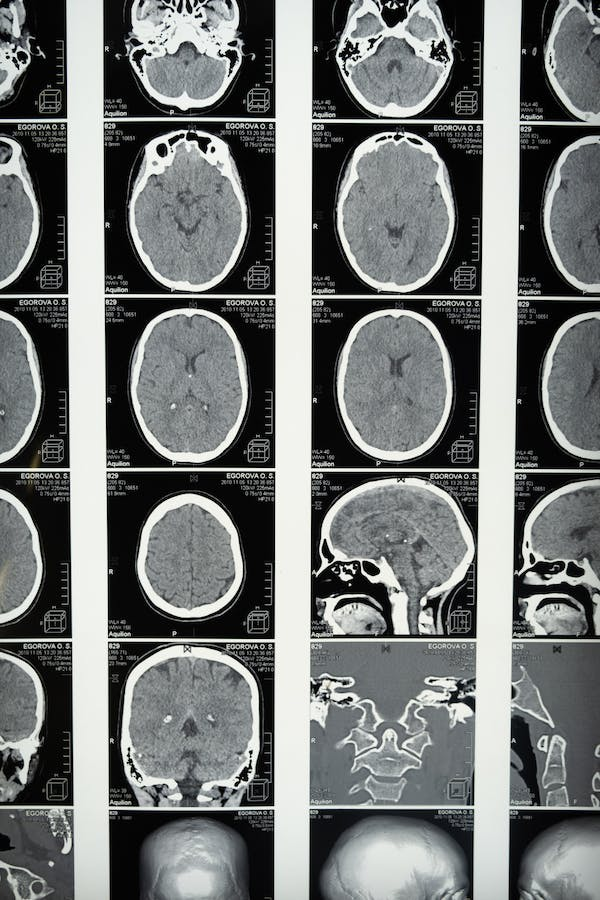

Mirando en el cerebro

Principalmente, la característica más común en la tomografía computarizada cerebral específicas (TC) para la encefalitis por varicela es hipodensidad en los lóbulos temporales que, en ocasiones, afecta también al lóbulo frontal. Además, los ganglios basales suelen permanecer intactos. En el caso de la resonancia magnética (RM), los hallazgos típicos para esta afección son cambios edematosos con hipodensidad en los lóbulos temporales y lóbulos frontales inferiores, mientras que los ganglios basales permanecen indemnes (Ellis et al., 2015).